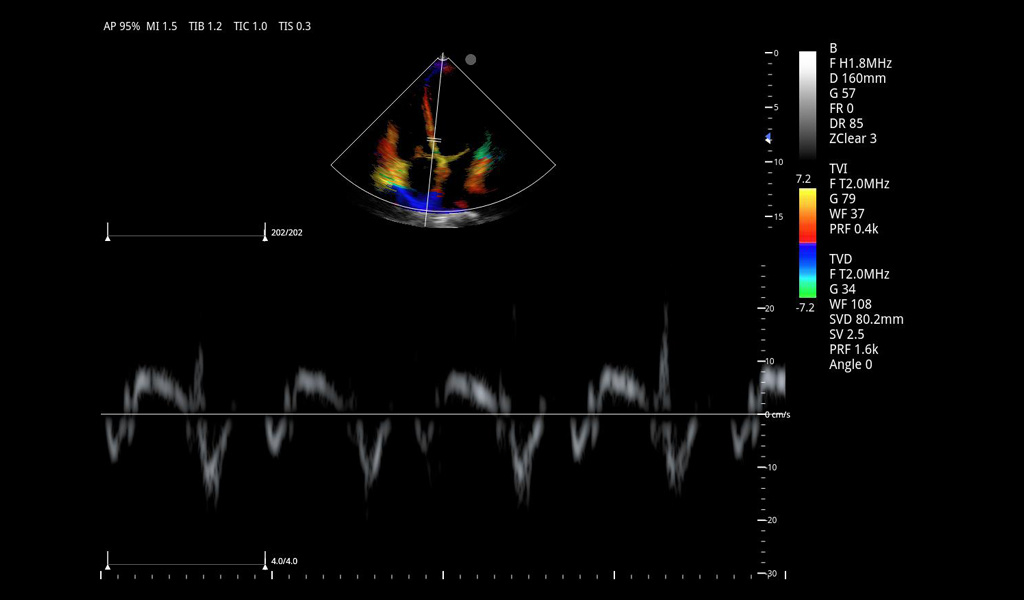

Excelentes imágenes clínicas

|

|

|

|

|

|